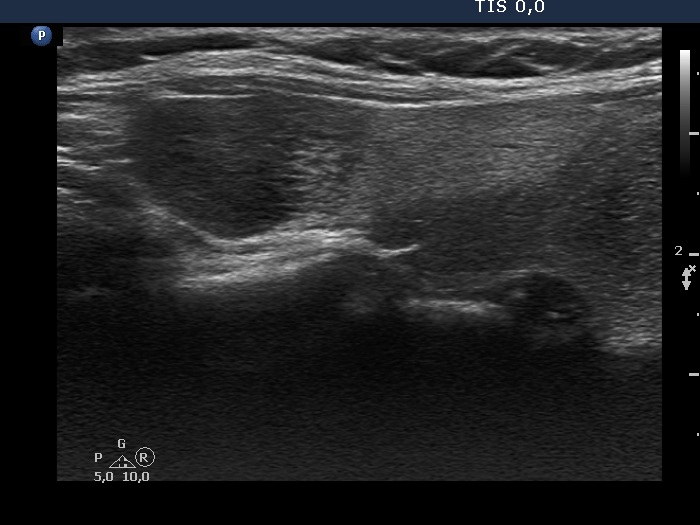

Second examination 3 years later (second, fourth and sixth rows of images):

Ultrasonography. Compared with the previous examination, both the number and the size of discrete lesions in the thyroid have increased.